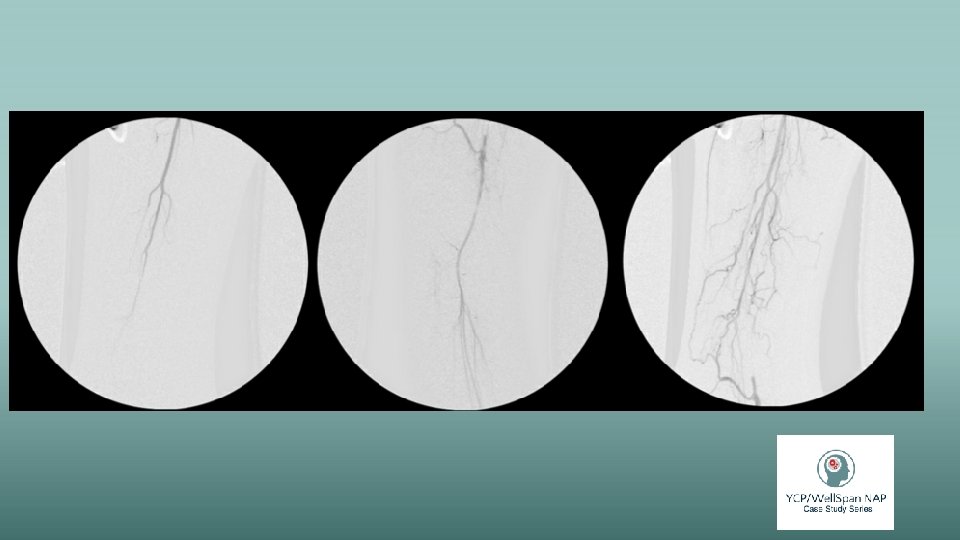

Preoperative evaluation and exam • Extremely thin BMI: 19. 1 • Sitting on the edge of the bed in significant pain and contracted • Pleasant and answered questions • Denies taking medications or any recent medical care • Endorsed 25 beers daily • Airway exam concerning for limited ROM • EKG: NSR • VSS: 99. 1, HR 89, BP 92/56 • Pain: 7/10 - 10/10 • Open draining black wound • Doppler US showed limited arterial blood flow distal to the knee • Morphine ER BID, Vancomycin and Zosyn • Lisinopril held for low BP

Intraoperative course • Extremely irritable and noncooperative • 10/10 pain and photophobia • 36 hours since his last drink • BP: 82 -95/49 -55 • Midazolam 2 mg was given prior to OR • Propofol, fentanyl, rocuronium • Hypotension was treated with phenylephrine and ephedrine • 16 g IV and radial Artline were placed • Ketamine 50 mg was given as an infusion • Additional 3 mg midazolam in divided doses • Additional rocuronium